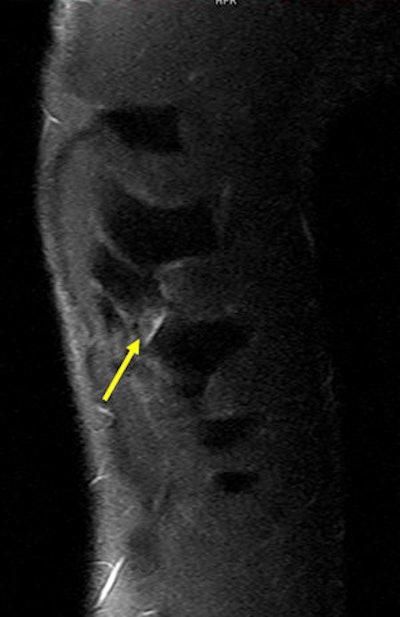

A 26-year-old rugby player with a left-sided thoracic injury. Oblique coronal MR image (short tau inversion-recovery sequence) shows a chondral fracture of the eighth rib. Yellow arrow points to the site of fracture, where a small amount of fluid accumulation is depicted as hyperintensity. Image courtesy of Dr. Daichi Hayashi, PhD.Traumatic thoracic injuries in rugby players are much less common than lower limb injuries, but the players are relatively more prone to such injuries due to the minimal protective wear compared to other contact sports such as American football, in which players wear protective clothing and helmets, he explained in an award-winning e-poster on this topic at the Chicago congress.

Rib injuries among rugby players tend to be most common in the fifth and ninth ribs, and they are often missed with conventional radiography and ultrasound. Always perform a CT scan with a multiplanar reconstruction (MPR) and volume-rendering technique (VRT), and use both CT and MRI for the acute stage, recommends Hayashi and his co-authors from the department of radiology at Klinikum Augsburg, Germany, the Australian Sports Commission, and Drs. Van Wageningen & Partners, Somerset West, South Africa. It is also necessary to consider nuclear medicine imaging for the delayed stage.

For an MRI examination of a suspected rib injury, the patient should be in a prone position, a marker should be placed, and axial and oblique coronal STIR (short TI inversion recovery) sequences should be obtained. T1-weighted sequences are not useful, and artifacts can be expected due to pulsation and breathing, they stated.